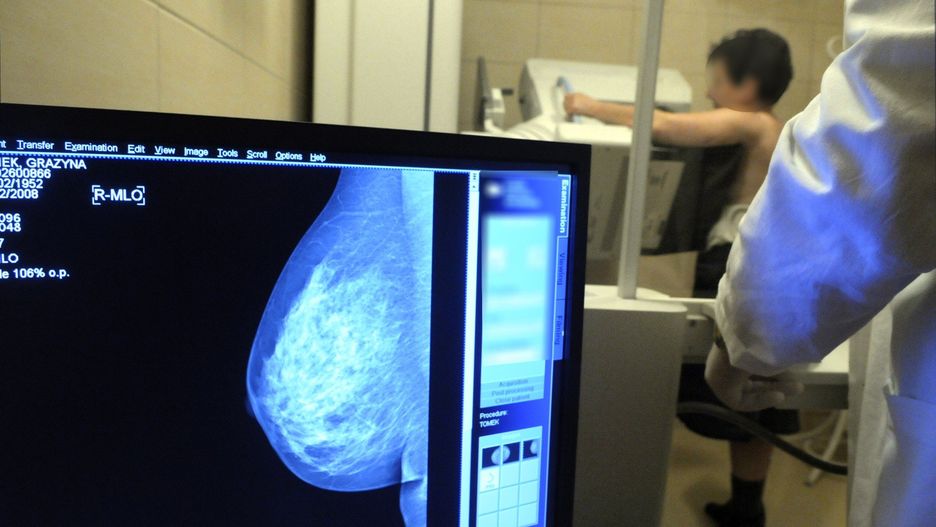

Profilaktyka to nie strach – to troska. Już 24 maja również w Obornikach odbędzie się kampania „Badamy nie tylko MAMY” – ogólnopolska akcja bezpłatnych badań i edukacji zdrowotnej, która przypomina kobietom w każdym wieku, jak ważne są regularne badania piersi.

Profilaktyka raka piersi to najważniejsza rzecz w drodze po zdrowie.Profilaktyka raka piersi to najważniejsza rzecz w drodze po zdrowie.

Rak piersi to najczęstszy nowotwór złośliwy wśród kobiet w Polsce. Rocznie diagnozowany jest u tysięcy pań – często zbyt późno. Tymczasem wczesne wykrycie znacznie zwiększa szanse na całkowite wyleczenie. Dlatego organizatorki kampanii – Federacja Stowarzyszeń Amazonki – przypominają: „Badamy nie tylko MAMY”, ale każdą kobietę – bez względu na wiek, miejsce zamieszkania czy status zawodowy.